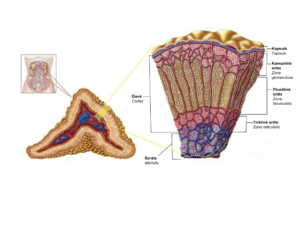

| مناطق الغدد الكظرية | |

| مناطق الغدد الكظرية | |

تشير دراسة الحالات المبلغ عنها إلى أن معظم أورام الغدة الكظرية الغدية تحدث بسبب الانتشار الورمي للخلايا القشرية الكظرية داخل الطبقات الثلاث المتميزة لقشرة الغدة الكظرية. في البشر، تتكون قشرة الغدة الكظرية ثلاث مناطق مركزية بما في ذلك منطقة الكبيبية ، المنطقة الحزمية و منطقة الشبكية أنه في ظل الظروف العادية تستجيب لمطالب الجسم الفسيولوجية لهرمونات الستيرويد. تعتبر قشرة الغدة الكظرية عضوًا ديناميكيًا يتم فيه استبدال الخلايا الشائخة بخلايا متمايزة حديثًا. هذا التجديد المستمر يسهل إعادة تشكيل الأعضاء مما يساهم في الخصائص الديناميكية لقشرة الغدة الكظرية.. [8] بالمقابل ، يُعتقد أن الفسيولوجيا التطورية لقشرة الغدة الكظرية تلعب دورًا محوريًا في تكوين أورام الغدة الكظرية الغدية. ومن ثم ، فإن الآليات الجزيئية المشاركة في التطور الطبيعي للغدد الكظرية تشبه السيوف ذات الحدين التي يمكن أن تؤدي إلى تكوين أورام داخل قشرة الغدة الكظرية. علاوة على ذلك ، تشير الدراسات الحديثة إلى أن الطفرات التي تؤثر على المسارات الجزيئية لمنطقة قشر الكظر يمكن أن تحفز الانتشار غير الطبيعي وتكوين الورم. من خلال هذه الدراسات ، تم التعرف على أحادي فوسفات الأدينوسين الحلقي المعتمد على بروتين كيناز أ كوسيط رئيسي لإفراز الكورتيزول ، وقد تورطت الطفرات المرتبطة بخلل تنظيم مسارات أحادي فوسفات الأدينوسين - بروتين كيناز أ في الفيزيولوجيا المرضية لقشرة الكظر.[9]

الفيزيولوجيا المرضية